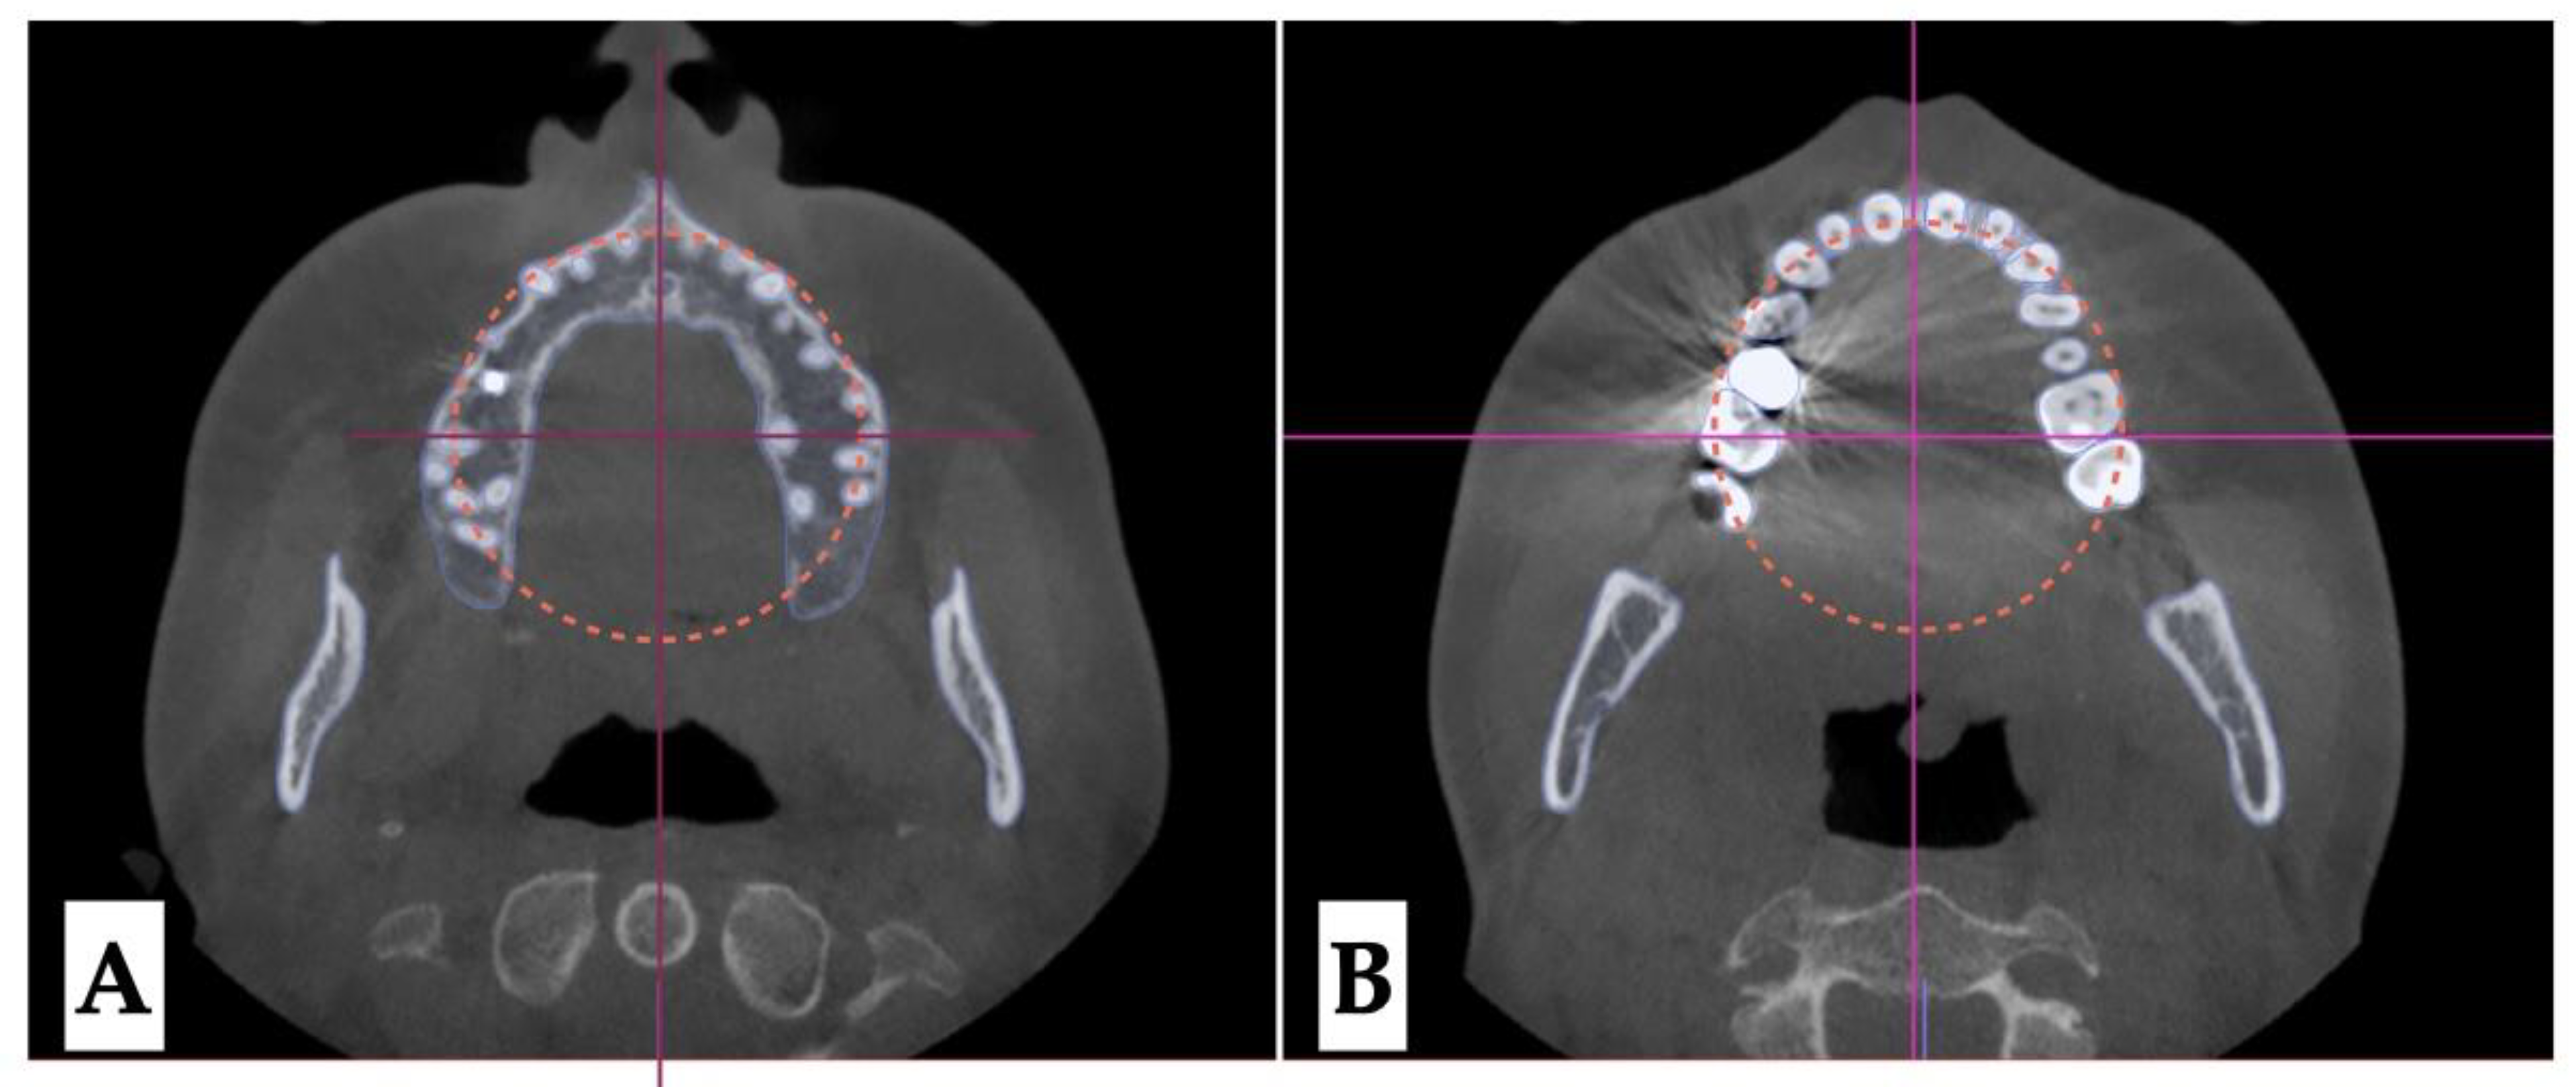

Dento-alveolar analysis: dento-alveolar slicing was performed at different levels of the maxillary teeth roots (apical third, half of the root length, and lower third of the root length) to evaluate the symmetry of root positions relative to the buccal cortical plate of the maxillary alveolar process. Upper left quadrant showed clear asymmetry of the root positions with the closer proximity to the buccal cortical plates. (Figure 5 and Figure 6). Palatal plane orientation before treatment is parallel to the constructed Orbital plane as seen on Figure 6, while the maxillary occlusal plane shows definitive canting with the left side occlusal plane located below the right side.

Figure 5. Pre-treatment axial plane slices visualization: A- axial slice at the level of the ANS with the skull oriented to all three reference planes, this view shows closer proximity of the root arises of the left upper quadrant to the buccal cortical plate of the alveolar process, B - axial view in the same orientation at the level of the 1/2 root length following the same pattern of buccal cortical plate proximity of the UL maxillary roots, C - ANS-PNS and Orbital planes orientation at the level of the lower 1/3 of the root length.

Figure 6. Pre-treatment axial plane slices visualization: A- axial slice at the level of the ANS with the skull oriented to all three reference planes, this view shows closer proximity of the root arises of the left upper quadrant to the buccal cortical plate of the alveolar process, B- ANS-PNS and Orbital planes orientation at the level of the lower 1/3 of the root length, both views showing asymmetry in UL roots positioning relative to the constructed circle with vertical diameter coinciding with the ANS-PNS plane.